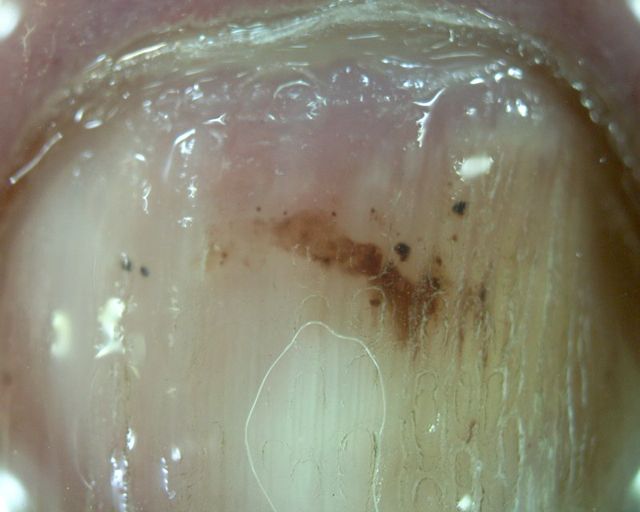

Nail haemorrhage = النزف تحت الظفر